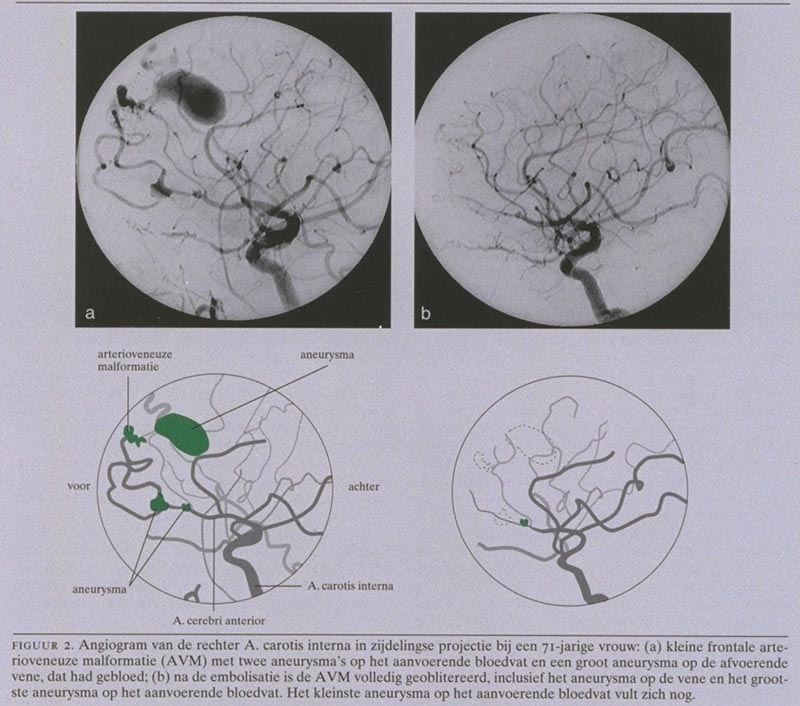

In een periode van 35 maanden werden door de werkgroep Neurovasculaire Interventie Tilburg 115 patiënten met een AVM gezien. De gemiddelde leeftijd was 41,8 jaar (uitersten: 6-72). De voornaamste klinische manifestatie was bij 65 patiënten (56,5) een bloeding, bij 31 patiënten (27,0) epilepsie, bij 7 patiënten (6,1) neurologisch uitval en bij 2 patiënten (1,7) hydrocefalus; bij 10 patiënten (8,7) werd de AVM bij toeval gevonden. De behandeling bestond uit operatie, stereotactische bestraling met het ‘gamma-knife’ en embolisatie. Embolisatie vond voornamelijk plaats teneinde de AVM te verkleinen om operatie of bestraling mogelijk te maken.

Van de 115 patiënten waren er 5 naar de werkgroep verwezen voor alleen een behandeladvies; bij hen vond eventuele behandeling elders plaats. Van de resterende 110 patiënten werden 84 wel behandeld (76,4) en 26 (23,6) werden om uiteenlopende redenen niet behandeld. Van de 84 behandelde patiënten werden 17 (20,2) alleen geopereerd, 17 (20,2) werden alleen bestraald en 12 (14,3) ondergingen alleen embolisatie. Operatie na embolisatie vond plaats bij 8 patiënten (9,5) en bestraling na embolisatie bij 26 (31,0). Bij 4 patiënten vond om uiteenlopende redenen een ongebruikelijke combinatie van deze behandelingen plaats.

Voorlopig was bij 35 van de 84 behandelde patiënten (41,7) de AVM geheel verwijderd of geoblitereerd; 39 patiënten wachtten nog op het definitieve resultaat van bestraling. Bij 5 patiënten werd opzettelijk een partiële embolisatie uitgevoerd. Bij 5 patiënten (6,0) werd het vooraf gestelde doel niet bereikt met embolisatie. De morbiditeit bedroeg 4,8 (4 patiënten) en de sterfte 1,2 (1 patiënt).